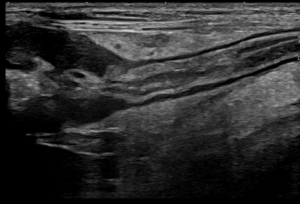

- 画像検査: 腎結石、尿管結石、尿管の拡張が確認されました。

- 尿検査: 尿中に細菌と白血球、細菌の貪食像がみられました(画像参照)。

- エコー検査: 著しい尿管の拡張と腎盂の拡張。尿管径は5.7mmと、通常(1mm以下)より大きく拡張していました。